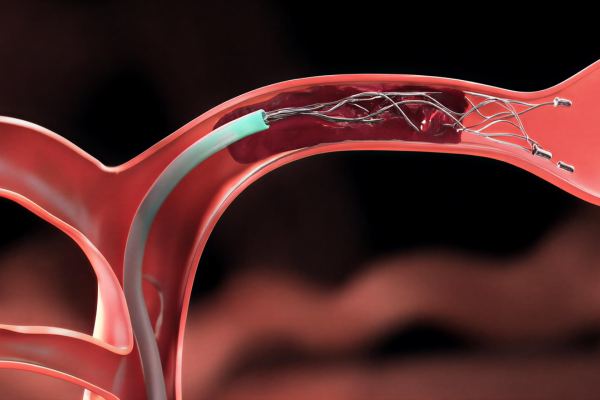

Minimally invasive procedure sealing aneurysms to prevent rupture and protect brain circulation safely.

Minimally invasive technique using soft coils to block aneurysm flow, preventing rupture and ensuring long-term vascular stability.

Aneurysm coiling is a minimally invasive procedure used to treat brain aneurysms by preventing rupture. It is performed when weakened blood vessels balloon and pose a serious risk of bleeding.

Using thin catheters, soft coils are placed inside the aneurysm to block blood flow, reduce pressure, and safely prevent future bleeding.